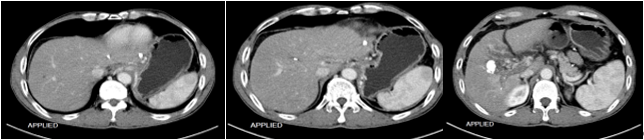

影像学检查:2016-11-16,CT 动脉期:

2016-11-16, CT 门脉期: